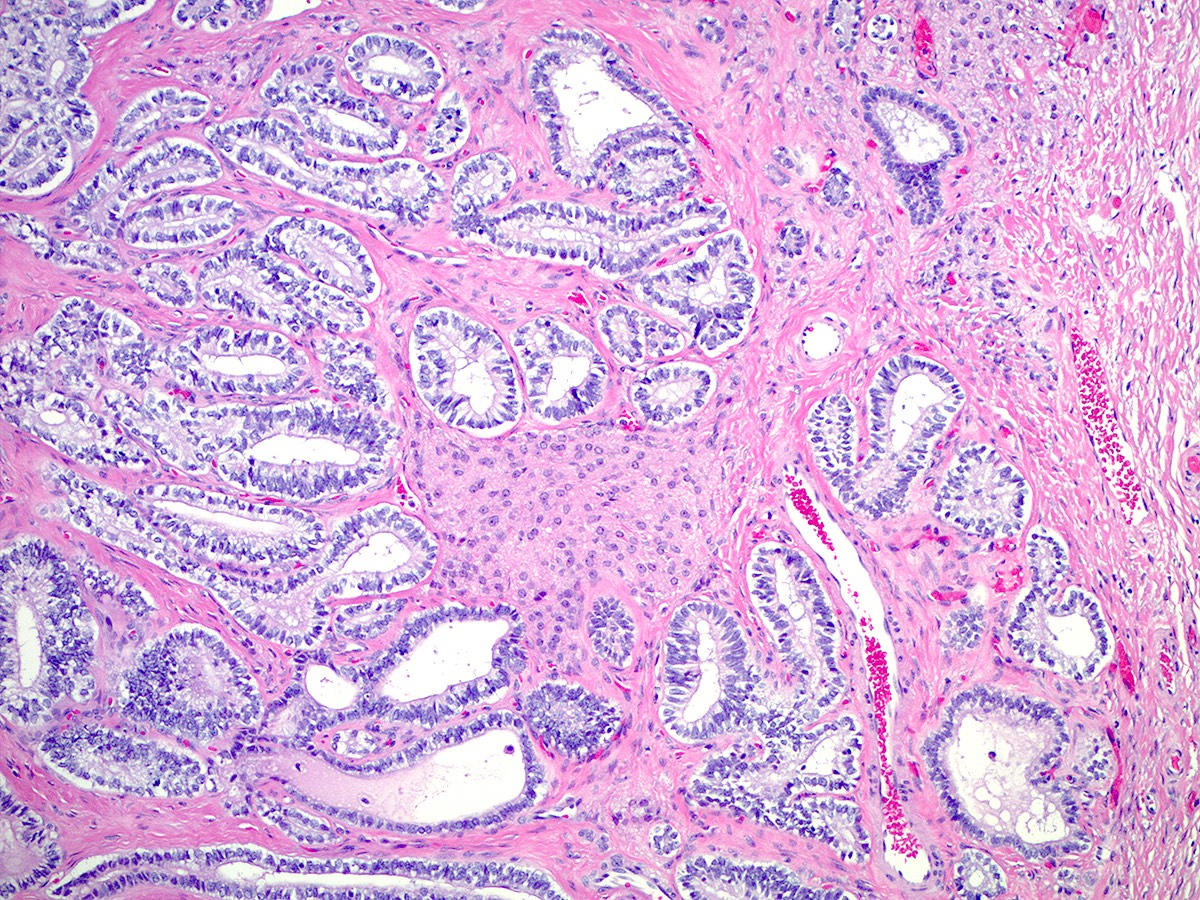

Microscopic (histologic) description

- Moderately differentiated

- Typically has a diffuse or lobulated architectural pattern and may show alternating hypo and hypercellularity on low magnification

- Sertoli cells form compressed tubules, cords or diffuse sheets and have hyperchromatic, oval or spindled nuclei with mild to moderate atypia and occasional mitotic figures (average 5 per 10 high power fields)

- Rare small clusters of Leydig cells are admixed with the Sertoli cell component

Microscopic (histologic) images